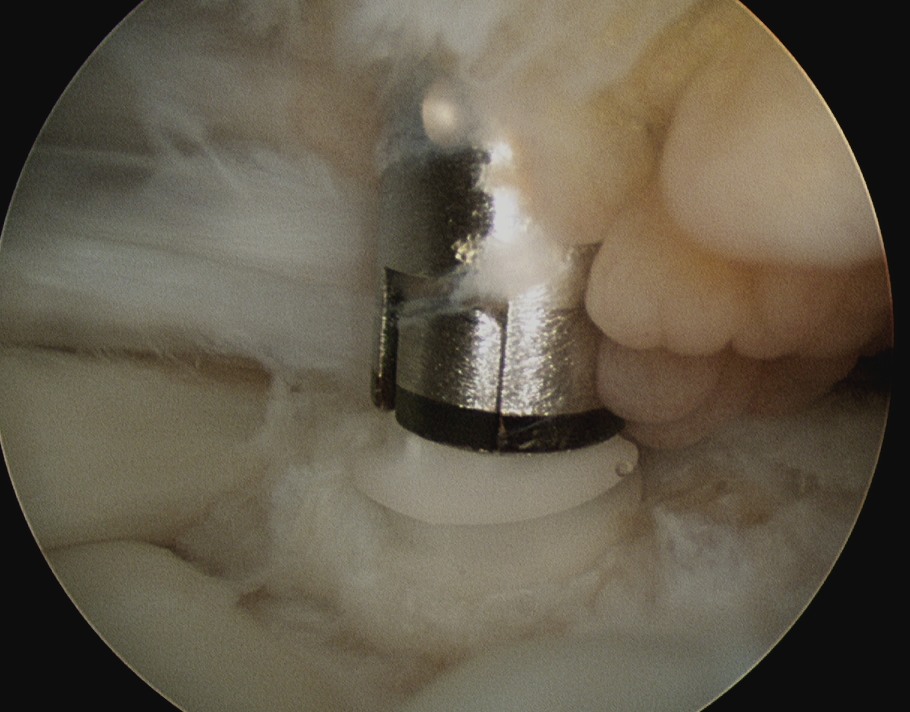

D. Transosseous equivalent / suture bridge

Technique

- biomechanically replicate tradional open transosseous

- sutures crossed as below in double row

- aiming to increase contact between cuff and footprint

Double row

- either pass second lateral row of anchors or

- use foot print anchors, retrieve previous sutures

- can make suture bridge configuration

- check repair via lateral portal